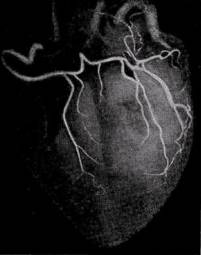

Правая и левая коронарные артерии были условно разделены соответственно на три и семь сегментов.

посегментное деление коронарных артерий сердца: А — правая коронарная артерия, Б — левая коронарная   артерия

В правой коронарной артерии выделено три сегмента:

· отрезок артерии от устья до отхождения ветви — артерии острого края сердца (длина от 2 до 3,5 см);

· участок артерии от ветви острого края сердца до отхождения задней межжелудочковой ветви правой коронарной артерии (длина 2,2—3,8 см);

· задняя межжелудочковая ветвь правой коронарной артерии. По нашим данным, только у 14% больных она достигала верхушки сердца, анастомозируя с передней межжелудочковой ветвью левой коронарной артерии.

· Правая коронарная артерия у большинства больных имеет магистральный тип деления и играет важную роль в васкуляризации сердца, особенно его задней диафрагмальной поверхности. У 25% больных в кровоснабжении миокарда выявлено преобладание правой коронарной артерии.

В левой коронарной артерии выделено семь сегментов:

· Начальный отдел левой коронарной артерии от устья до места деления на главные ветви, обозначается, как I сегмент длина его от 0,7 до 1,8 см.

· Первые 4 см передней межжелудочковой ветви левой коронарной артерии разделены на два сегмента по 2 см каждый — II и III сегменты. Диаметр II сегмента артерии колеблется от 2 до 4,5 мм

· Дистальный участок передней межжелудочковой ветви составил IV сегмент. Она может заканчиваться у верхушки сердца, но обычно (по нашим наблюдениям, у 80% больных) продолжается на диафрагмальной поверхности сердца, где встречается с конечными веточками задней межжелудочковой ветви правой коронарной артерии и участвует в васкуляризации диафрагмальной поверхности сердца.

правовенечный тип коронарного кровообращения, хорошо развиты задние межжелудочковые ветви

· Огибающая ветвь левой коронарной артерии до места отхождения ветви тупого края сердца - V сегмент (длина 1,8-2,6 см).

· Дистальный участок огибающей ветви левой коронарной артерии чаще представлен артерией тупого края сердца — VI сегмент отходит под прямым углом по отношению к главному стволу и в 47,2% достигает верхушки сердца.

· Диагональная ветвь левой коронарной артерии (VII сегмент) идет по передней поверхности левого желудочка вниз и вправо, погружаясь затем в миокард. Диаметр ее начальной части от 1 до 3 мм. При диаметре менее 1 мм сосуд мало выражен и чаще рассматривается как одна из мышечных ветвей передней межжелудочковой ветви левой коронарной артерии.